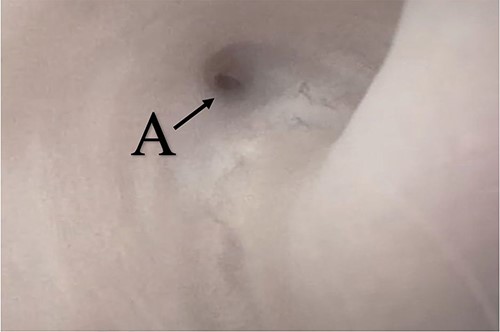

A 38-year-old male was referred to our tertiary hospital due to recurrent urethral stricture for further evaluation and management. His history revealed multiple failed attempts of DVIU, anastomotic urethroplasty and urethroplasty with pedicled fasciocutaneous flap in 2019. Nine months after his surgery, he had complete retention due to stricture recurrence and he underwent multiple dilatations and DVIU but his stricture keep recurring. He was referred to us for definitive management. He was on a suprapubic catheter. Initial workup included retrograde, antegrade cystoscopy and urethrogram. First, an antegrade cystoscope was introduced. The bladder neck, internal sphincter and verumontanum were identified. However, there was no external sphincter due to damage from the previous procedures. A pinpoint opening in the dorsal area of the urethra was seen about 1-cm distal to the verumontanum (Fig. 1, lumen A). Also, a blind-ended urethra in the ventral area was identified (Fig. 2, lumen B). It is most likely from the previous flap. Additionally, the retrograde urethrogram showed that the contrast was only going from the pinpoint hole in the dorsal side of the urethra Fig. 3. Retrograde cystoscopy also showed a blind-ended in the proximal bulbar urethra. We could not identify the small hole that we saw from the antegrade cystoscopy. After initial workup, he was counseled in the clinic for dorsal only buccal mucosal graft (BMG) urethroplasty for which he agreed.

(lumen A): A pinpoint opening in the dorsal area of the urethra as pointed in the arrow.